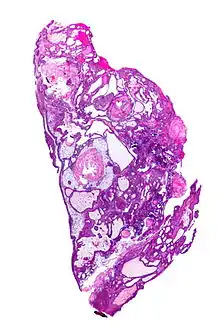

Very low magnification micrograph of an adamantinomatous craniopharyngioma. HPS stain.

On macroscopic examination, craniopharyngiomas are cystic or partially cystic with solid areas. On light microscopy, the cysts are seen to be lined by stratified squamous epithelium. Keratin pearls may also be seen. The cysts are usually filled with a yellow, viscous fluid rich in cholesterol crystals. Of a long list of possible symptoms, the most common presentations include headaches, growth failure, and bitemporal hemianopsia.